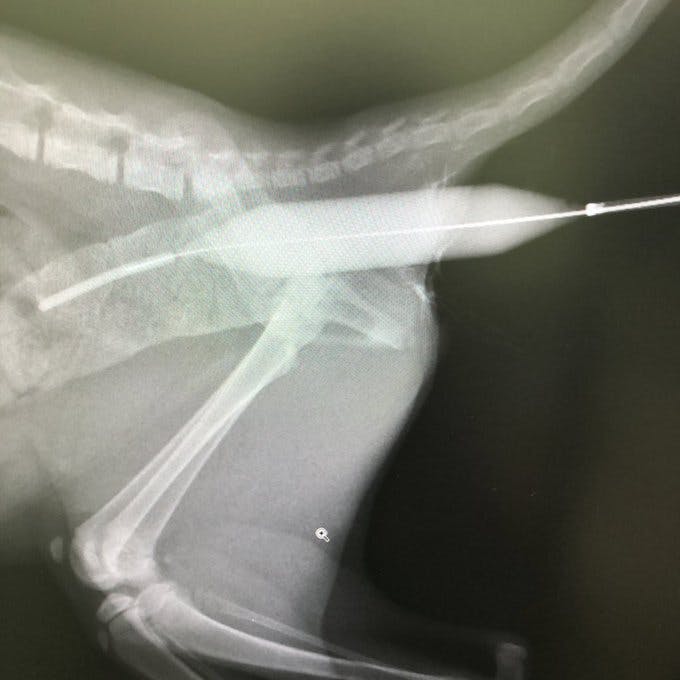

①は成長期の早いうちから実施したほうがよいと勧められたため、すでにバルーン拡張手術を2回実施しております。

7月17日(手術1回目)は7万7390円

7月26日(手術2回目)は器具代が入らなかったため、1万9000円でした。

手術の診療費明細書は下記写真のとおりです。

その他、通院費用や交通費を合わせると、2020年7月中は14万4425円必要でした。

拡張手術と毎日の投薬の結果、20㎜近くあった大腸は17㎜に収縮していることが判明しています。

5㎜の管を入れるのも困難だった肛門は、1.2㎜前後拡張を目標に少しずつ広がっています。

あんこの場合は、直腸と肛門がかろうじでつながっているので、まずは人工肛門の外科的手術の前に挿入したバルーンによる拡張手術に期待をかけています。